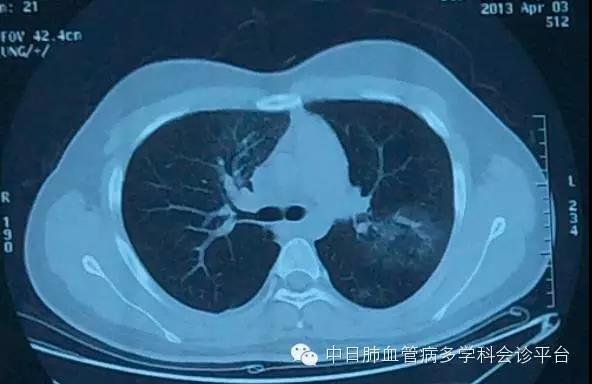

2013年4月3日 CT

患者为21岁男性,目前心脏彩超已提示肺动脉压力显著增高,结合其下肢深静脉血栓形成、肺栓塞病史,我们首先想到了是否为慢性血栓栓塞性肺动脉高压,回顾其2016年1月4日CTPA可以见到双侧(右侧明显)肺动脉主干内增厚的软组织影,部分血管内可见“蹼样征”,因此,考虑慢性血栓栓塞性肺动脉高压可能性大。